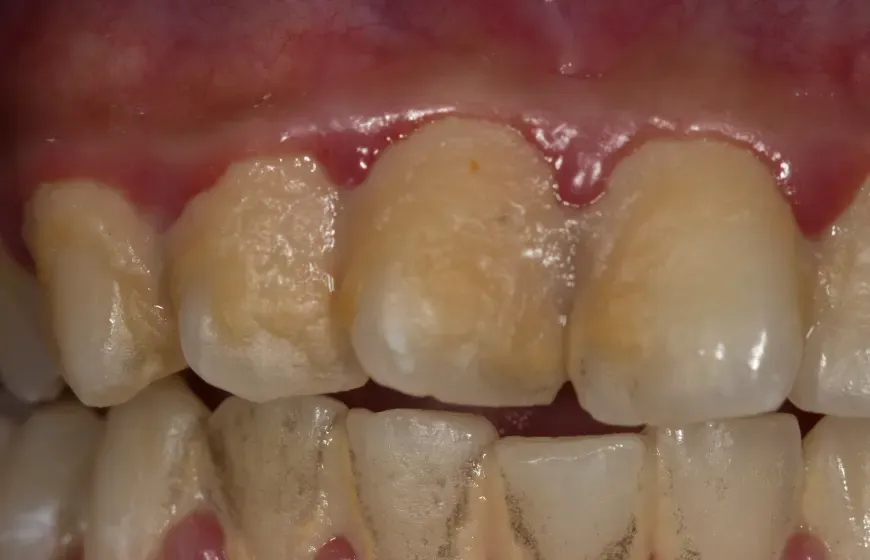

Ciemny nalot, który często pojawia się wzdłuż linii dziąseł, jest zazwyczaj połączeniem kilku czynników. Po pierwsze, jest to szybko postępująca próchnica. W warunkach kserostomii i braku higieny, próchnica rozwija się w zastraszającym tempie, a jej postępujące ubytki często przybierają ciemny, brązowy, a nawet czarny kolor. Po drugie, w środowisku ubogim w ślinę i z zalegającymi resztkami pokarmu, kamień nazębny odkłada się znacznie szybciej i może przybierać ciemniejsze zabarwienie. Dodatkowo, zniszczone, porowate szkliwo zębów łatwiej chłonie barwniki z pożywienia, napojów, a także dymu papierosowego, co potęguje efekt przebarwień i sprawia, że zęby wyglądają na znacznie bardziej zniszczone, niż są w rzeczywistości.

- Ciemna, rozległa próchnica: Szczególnie widoczna tuż przy linii dziąseł, zwłaszcza na przednich zębach. Często przybiera barwę od brązowej do niemal czarnej.

- Zęby wyglądające na "zjedzone": Są one sczerniałe, kruche i często ułamane blisko linii dziąseł, co sprawia wrażenie, jakby zęby były "wygryzione".

- Silne stany zapalne dziąseł: Dziąsła są zaczerwienione, opuchnięte i często krwawią podczas szczotkowania lub jedzenia.